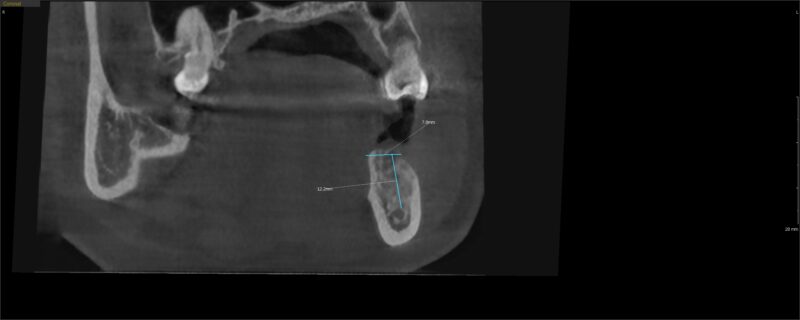

I saw the pt today and felt like the bone could be more dense in the extraction site. Looking at the photos you can see that the ridge was 9.7mm and now it’s 7.8mm after 4 months.

As far as size selection, I would be comfortable with a 4-4.5 mm width and a 8mm length. The position of your ruler over the site is not exactly on the bone (the lines extend out a little bit) so I would rather be a bit more conservative.